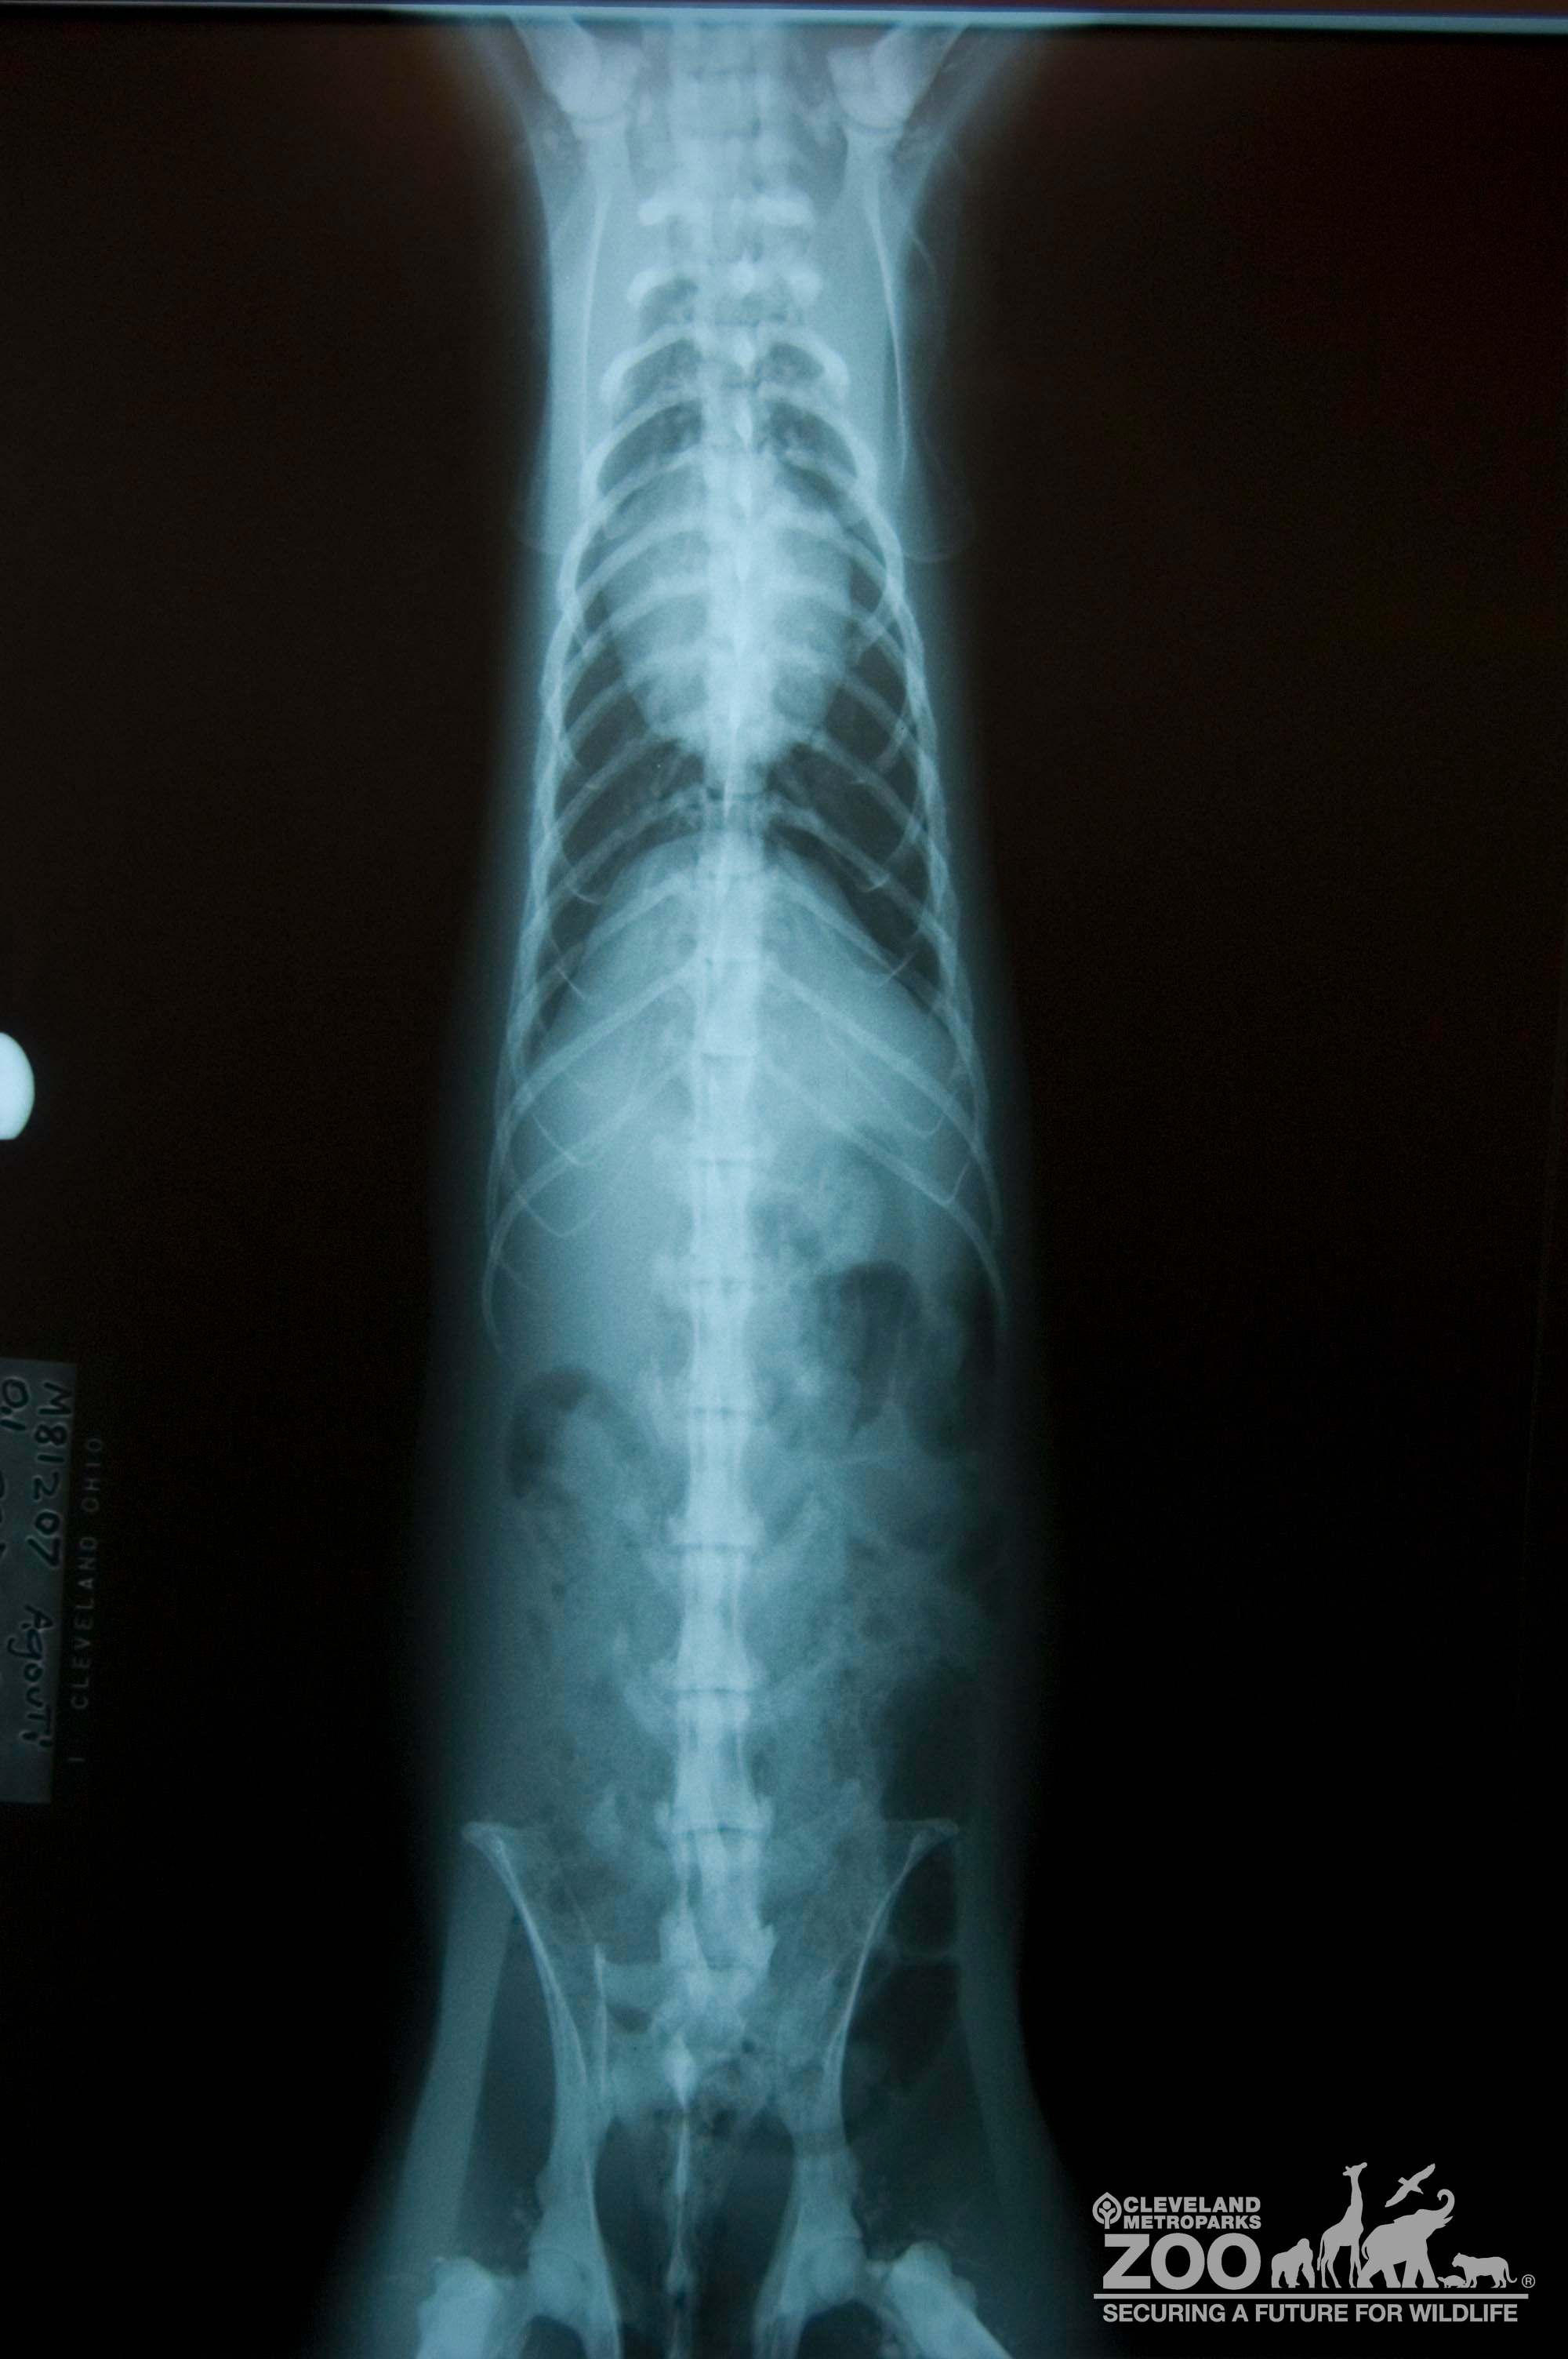

The Agouti in this photo has been x-rayed from the underside of the animal. The parts of Agouti's skeleton that are visible include it's pelvis, spine, ribcage, shoulder blades and some internal organs. The bones and organs of the Agouti are white in color while the background of the photo is completely black.